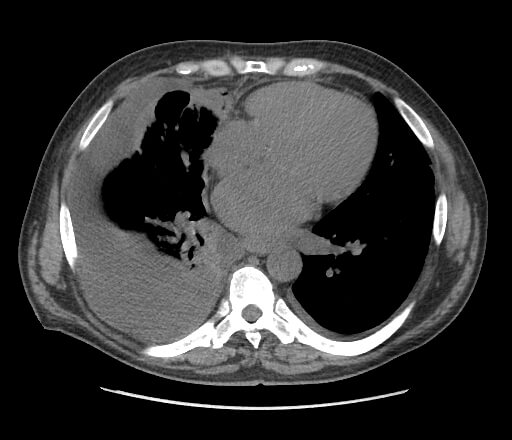

Palliative Care

Many of the procedures that are performed on a daily basis by IR have a role in the care of patients in the late stages of cancer. Whether it is the management of fluid that is needed in a patient with ascites or pleural effusions or the need for nutritional supplementation via a feeding tube (such as a gastrostomy or gastrojejunostomy tube), IR can perform these and other procedures to improve the quality of life of patients with advanced cancer.